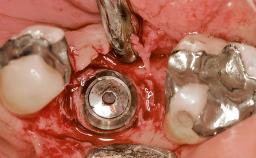

Ridge Preservation and Implant Placement for a Fixed Dental Prosthesis After a Car Accident

It is well known to clinicians that any removal of teeth will, over time, cause the dimensions of the alveolar ridge to be reduced by resorption of the bundle bone and by changes related to external modeling. This development is particularly evident in the crestal region with its thin buccal bone that consists of bundle bone almost entirely. The facial bone will rapidly resorb as blood supply from the periodontal ligament gets disrupted (Araújo and Lindhe 2005). There is no reason why traumatic tooth loss should not have the same consequences. It takes more than achieving implant osseointegration for a treatment outcome to be considered successful. No deficiency of bone or soft tissue is acceptable when an ideal esthetic outcome is the goal. Several articles (Sanz and coworkers 2011; Vignoletti and coworkers 2011) have reported on techniques of improving the alveolar ridge for implant treatment, notably focusing on protecting tissues from resorption.

Bone Augmentation Horizontal|Simultaneous|Sinus Floor Elevation|Staged

Augmentation Materials Xenogenous|Membrane